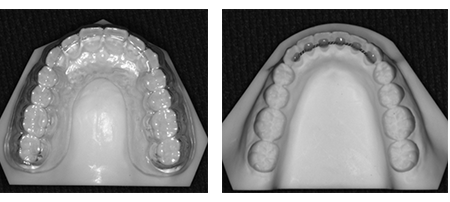

セラミック素材のブラケットを使う透明な矯正装置です。

金属やセラミック素材のブラケットにくらべると時間とともに多少の変色がありますが、あまり目立たない矯正装置です。

ワイヤーを白くコーティングしています。クリアブラケットと組み合わせると歯の色となじむので、ほとんど目立ちません。